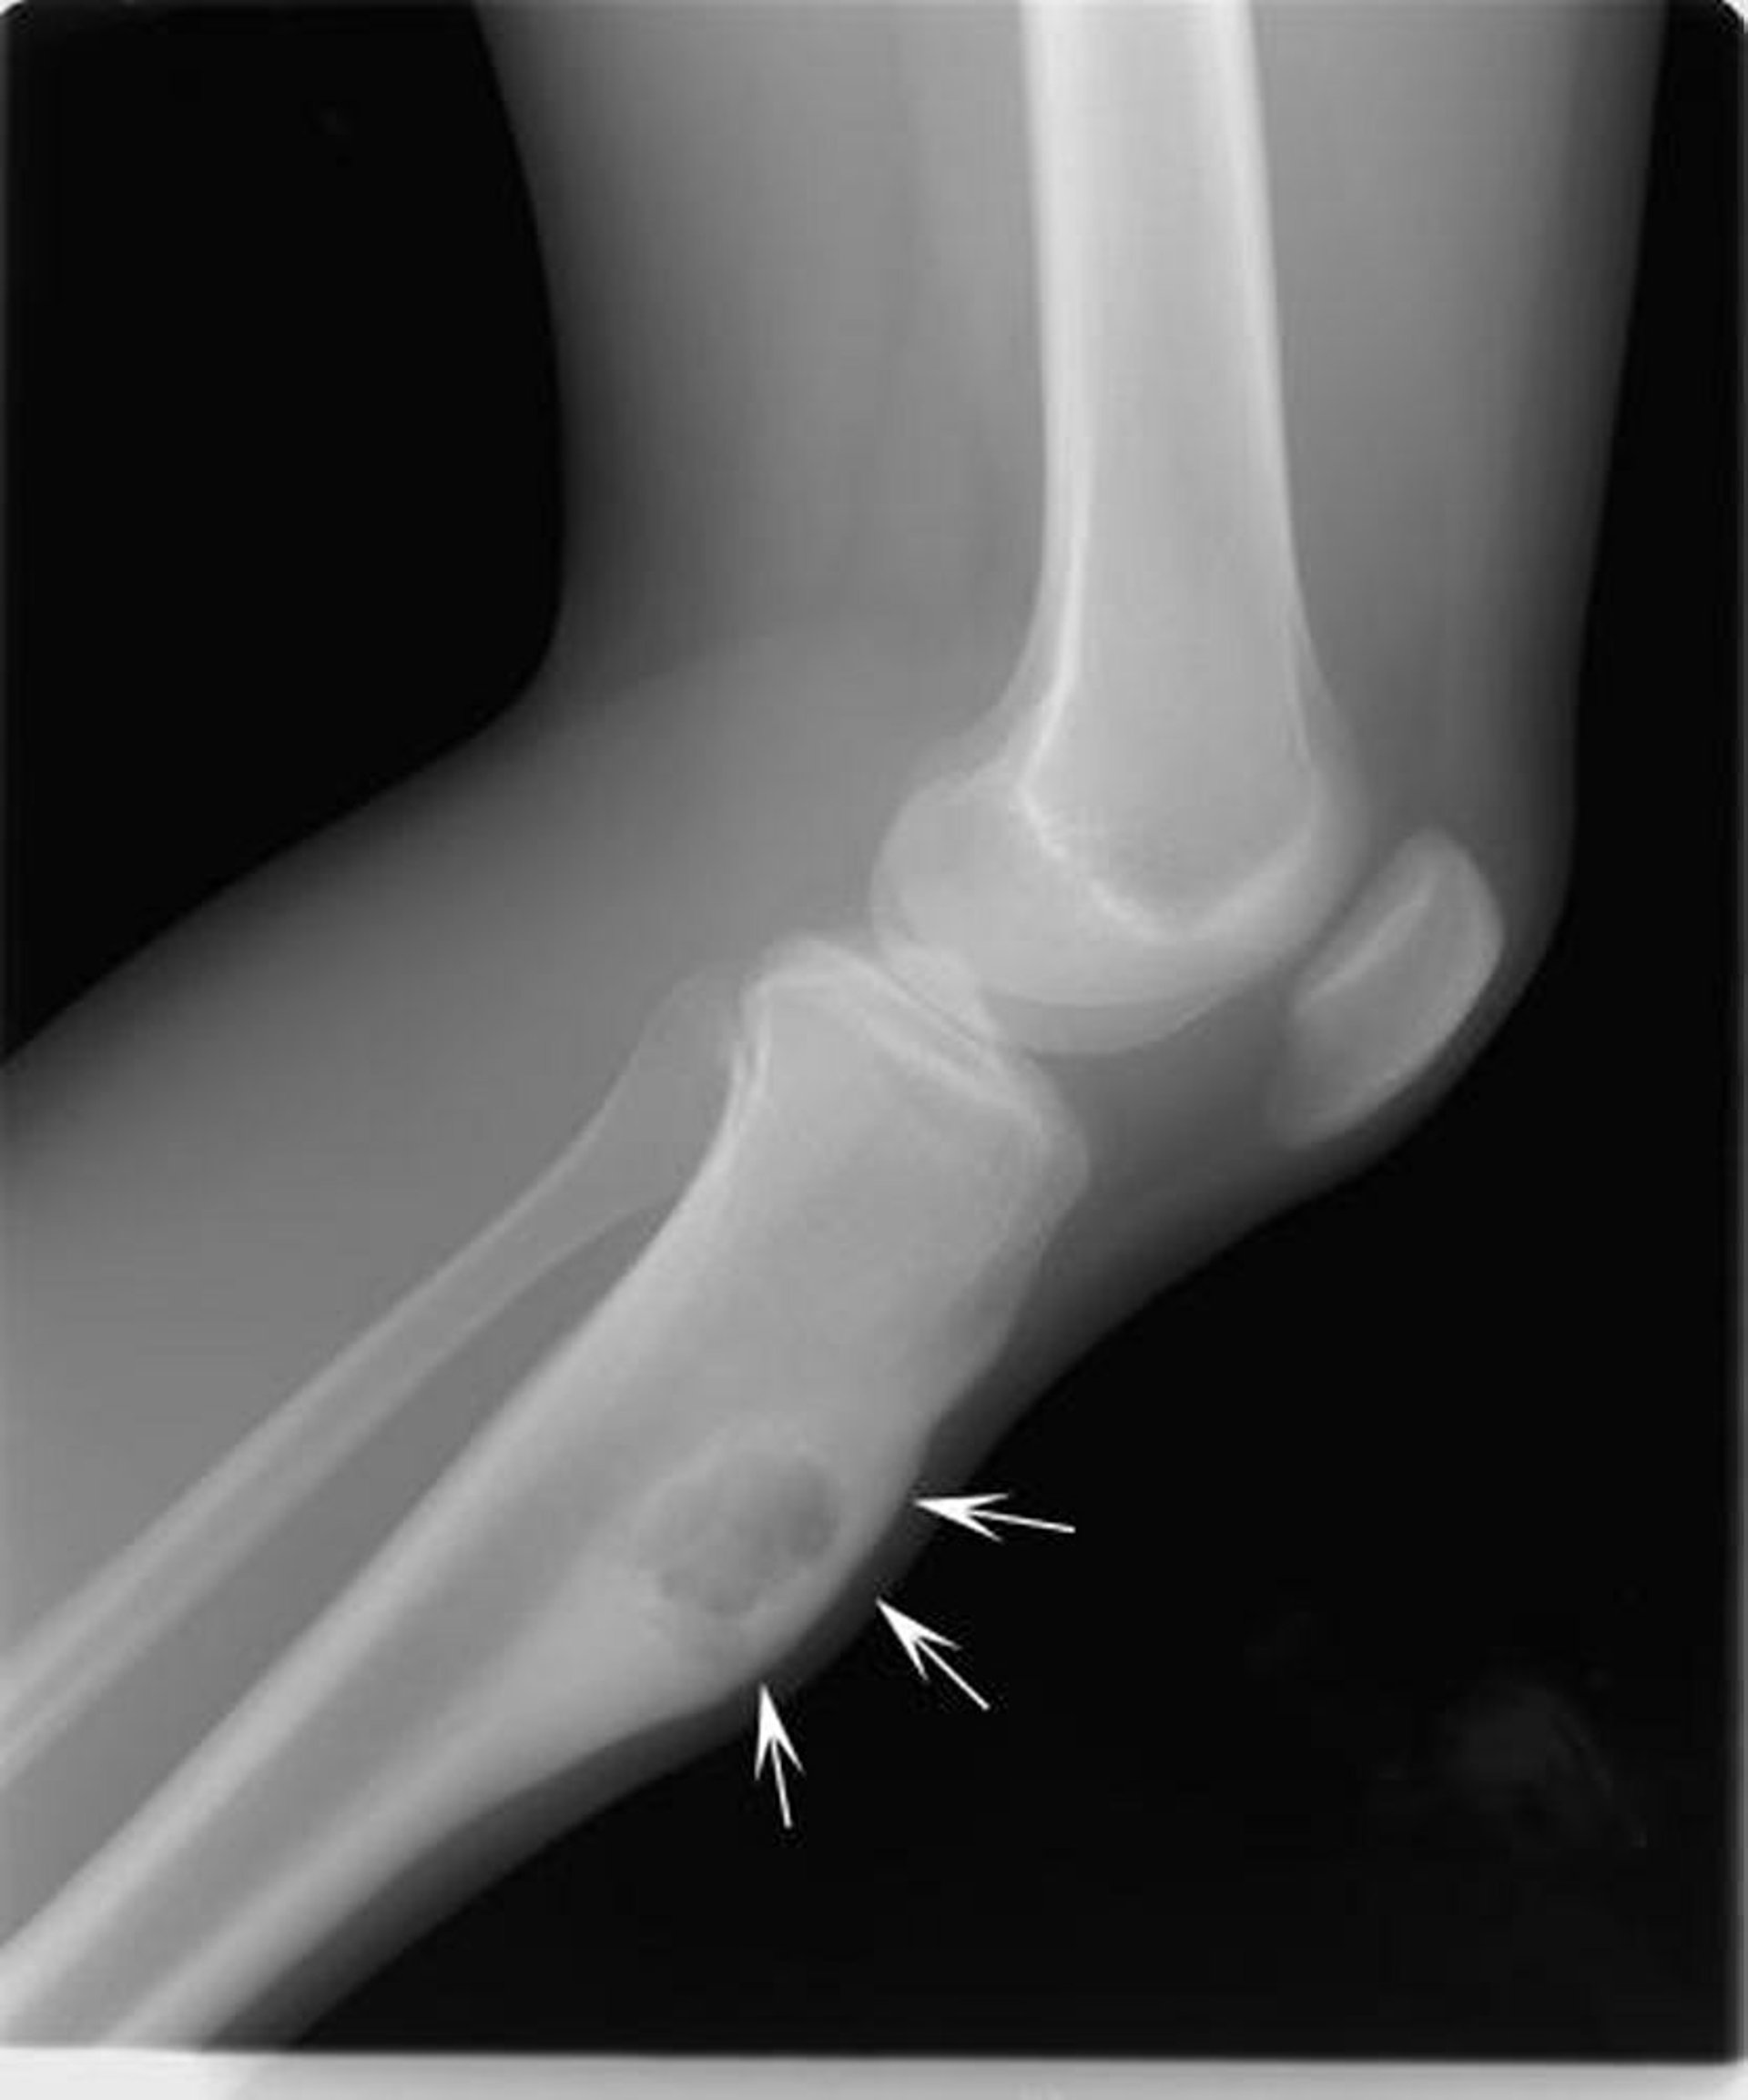

Cette radiographie du genou montre un chondromyxofibrome (flèches) sur le tibia, juste en dessous du genou.

Image publiée avec l’aimable autorisation des Drs Michael J. Joyce et Hakan Ilaslan.